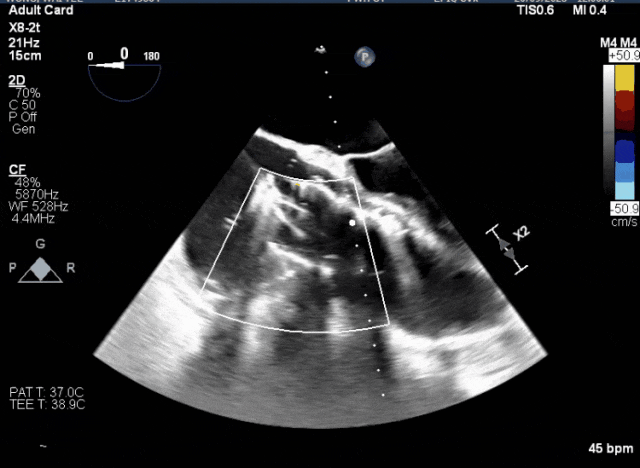

術中TEE成像困難,偽影干擾